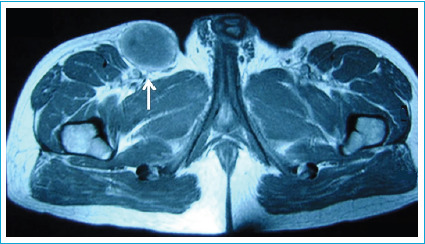

腹股沟肿块有多种原因,从腹股沟疝到软组织肉瘤。一个不太常见的原因是血管起源。与动脉动脉瘤不同,静脉动脉瘤很少出现,治疗经验也很少。一名32岁男性患者因左侧腹股沟肿块扩大,初步诊断为腹股沟疝而转介到我们诊所。多普勒超声显示一直径8厘米的动脉瘤性大隐静脉段位于腹股沟韧带下方。未完全切除扩张节段。大隐静脉动脉瘤的外科修复需要切除扩张节段,并根据静脉瓣膜衰竭进行完整的静脉切除。如果检测到大隐静脉动脉瘤,由于其衰弱性和可能破裂,应首先选择手术入路。

Inguinal masses have a large variety of causes, ranging from inguinal hernias to soft tissue sarcomas. One of the less prevalent causes is vascular origin. Venous aneurysms, unlike their arterial counterparts, are seen seldomly and experience in management of these cases is scarce. A 32-year-old male patient was referred to our clinic due to an enlarging left inguinal mass with a preliminary diagnosis of inguinal hernia. Doppler ultrasonography revealed an eight cm in diameter aneurysmatic Great Saphenous Vein segment located just below the inguinal ligament. Dilated segment was excised without complete resection. Removal of the dilated segment and performing complete venous resection depending on venous valvular failure constitutes surgical repair of Great Saphenous Vein aneurysms. Surgical approach should be primarily selected if Great Saphenous Vein aneurysm is detected due to its debilitating nature and possible rupture.